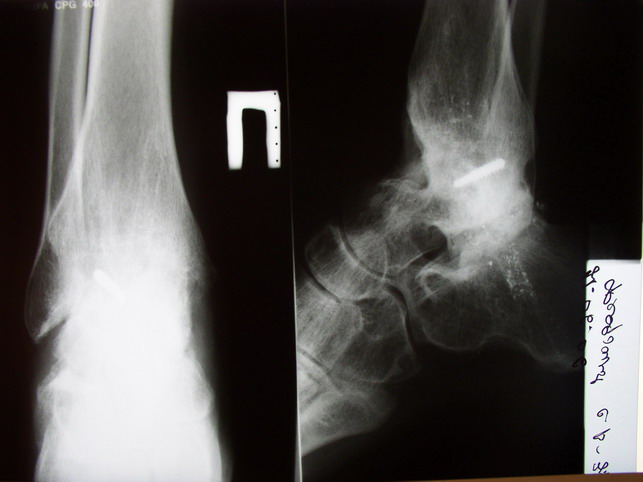

Глубокоуважаемые коллеги! Просим совета в лечении пациента с последствиями тяжелой сочетанной травмы. Пациент С., 41 года, по профессии бизнесмен, в сентябре 2005 г. пострадал в дорожно-транспортном происшествии (упал с мотоцикла). Диагноз: ЗЧМТ, ушиб головного мозга тяжелой степени. Открытый переломо-вывих левой таранной кости. Закрытые переломы лонной и седалищной костей слева. Был доставлен в НИИСП им. Н.В. Склифосовского. При ПХО раны выявлен открытый перелом левой таранной кости (III тип по Hawkins) с утратой вывихнутого тела таранной кости. Выполнена ПХО, фиксация голени и стопы стержневым аппаратом. Рана зажила без осложнений. Аппарат демонтирован через 1,5 месяца. В настоящее время больной предъявляет жалобы на боль в голеностопном суставе при нагрузке. Передвигается с опорой на костыли с дозированной нагрузкой на левую стопу.Голень и стопа фиксированы циркулярной пластиковой повязкой. Сохраняются остаточные явления ЧМТ (в виде сниженной критики к своему состоянию и определенной недисциплинированности в выполнении врачебных рекомендаций) Рентгенограммы – рис. 1, 2 (просим извинения за низкое качество рентгенограмм), схема – рис. 3. В качестве варианта хирургического лечения мы считаем возможным выполнить следующее вмешательство: артродез большеберцовой и пяточной костей в сочетании с артродезом переднего края большеберцовой кости и головки таранной кости с фиксацией спонгиозными винтами. Считаем выполнение артродеза переднего края большеберцовой кости и элементов I луча стопы необходимым для максимального восстановления опороспособности конечности. Однако выполнение операции в указанном объеме привело бы к относительному укорочению внутреннего свода стопы. Мы видим два пути решения данной проблемы: Вариант 1. Применение костного трансплантата (свободного или на сосудистой ножке) для замещения дефекта головки таранной кости и сохранения геометрии внутреннего свода стопы (рис 4). Преимущество: относительная простота операции. Недостаток: высокий риск замедленной консолидации или лизиса трансплантата. Вариант 2. Резекция участка пяточной кости с последующим остеосинтезом винтами для укорочения наружного свода стопы (рис 5, 6). Преимущества: сохранение собственного кровоснабжения всех синтезируемых участков костей. Недостатки: дополнительная травматизация, усугубление деформации стопы в виде нарушения наружного свода. Будем признательны за ваши предложения, включая возможные альтернативные варианты лечения.Заранее благодарны за добрые советы и поддержку. А. Федосов, О. Диденко, П. Иванов. Отделение множественной и сочетанной травмы НИИСП им. Н.В. Склифосовского, г. Москва.

Ваша дискуссия заставила перелистать свои наблюдения.

Среди повреждений таранной кости (Hawkins III-IV) с одновременной травмой лодыжек встретилось следующее (см. вложение). Пациент упал в колодец на глубину 10 метров (Х.2002 г.), госпитализирован с диагнозом: з/перелом шейки правой таранной кости (Hawkins IV) с переломовывихом тела назад и кнутри, закрытый перелом внутренней лодыжки и переднего края большеберцовой кости. Оперирован в первые 12 часов после травмы, выполнена открытая репозиция таранной кости, внутренним и передне-внутренними доступами, остеосинтез переломов шейки и тела губчатыми винтами, для реваскуляризации тела таранной кости первичный компрессионный над- и подтаранный артродез. Синтез внутренней лодыжки губчатым винтом. Удаление винтов через 1 год,2 мес. Получен анкилоз указанных суставов с сохранением длины конечности, полная реваскуляризация таранной кости, о чем говорит сращение ее переломов, отсутствие отеков и

цианоза стопы и голени. Компенсаторная подвижность переднего и среднего отделов стопы около 15-20 градусов за счет поперечного (Шопара) сустава стопы. Считаю оправданной подобную тактику, не смотря на угрожаемый прогноз (100% асептический некроз) по классифицкации Hawkins.